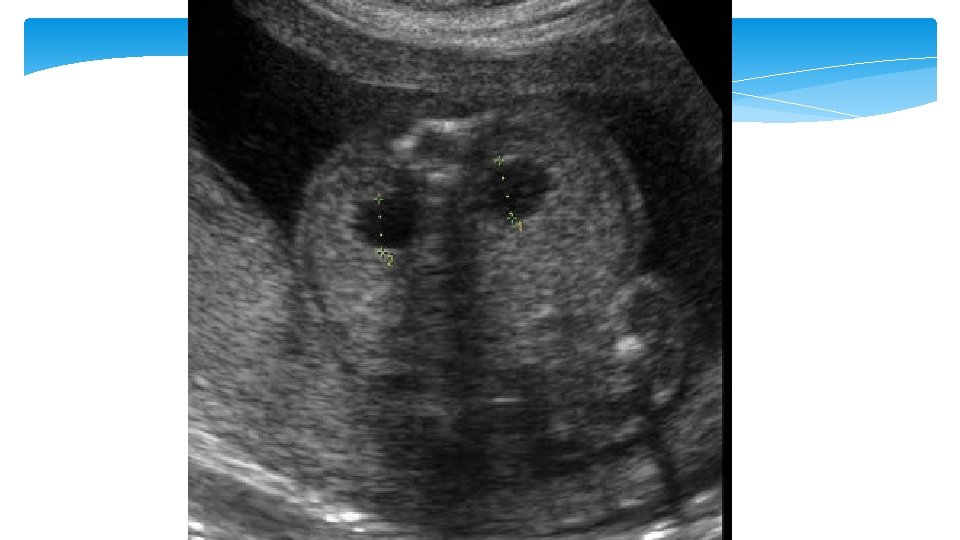

Renal Pyelectasis Mild pyelectasis refers to dilatation of the renal pelvis >4– 5 mm and <10 mm in the antero-posterior diameter measured in transverse section of the fetal abdomen. The cut-off value which is most frequently used in this dimesion is >4 mm in the 2 nd trimester and >7 mm thereafter

Renal Pyelectasis Dilatation of the renal pelvis is a common finding with an incidence reported to be between 0. 3 and 4. 5%. It is more common in male fetuses, and is often bilateral In unilateral it is more likely to present on the left side. according to one study unilateral pylectasis is associated with a higher rate of urinary tract abnormalities at birth